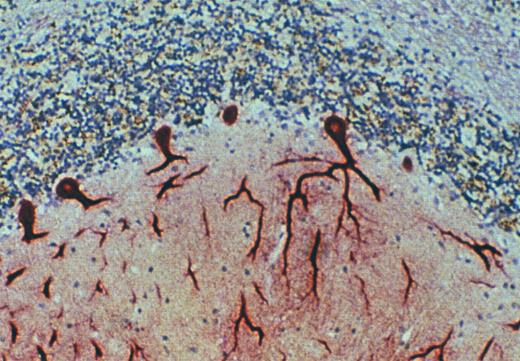

The physiologic significance of the novel multispecific RBC chemokine receptor, designated the Duffy antigen receptor for chemokines (DARC), initially appeared questionable because no pathologic or inflammatory consequences have been associated with the Duffy-negative phenotype. However, immunohistochemical staining of human tissues with anti-Fy6 provided additional insight into a potential physiologic function for DARC.22,101 Specific and intense staining with anti-Fy6 was observed with endothelial cells lining postcapillary venules throughout the body. Staining was not observed on endothelial cells lining capillaries or larger vessels, including venules, veins, arterioles, and arteries.101a Littoral cells, specialized endothelial cells that line the sinusoids in the red pulp of the spleen, were also strongly positive (Fig 3) as were the endothelial cells that line the bone marrow sinusoids and choroid plexus. Parallel chemokine binding experiments confirmed the presence of a high-affinity receptor having a promiscuous chemokine binding repertoire in membrane fractions from kidney and spleen.22,100 Endothelial cells lining the hepatic sinusoids lacked immunoreactivity. Tissue from individuals of the Fy(a−b−) erythroid phenotype were also examined and found to react with anti-Fy6 in a fashion identical to tissue from Duffy-positive individuals.22 Interestingly, endothelial cells of larger vessels were observed to react with anti-Fy6 under conditions of inflammation (eg, temporal arteritis, thrombophlebitis, omphalitis), suggesting upregulation of DARC under these conditions.101a

Immunohistochemistry of spleen using the anti-Duffy MoAb, anti-Fy6. Analysis was done on both freshly obtained and archival specimens of spleen. Anti-Fy6 reacts with specialized endothelial cells (littoral cells) lining the sinusoids in the red pulp. Endothelial cells lining arterioles, venules, arteries, and veins did not stain with anti-Fy6. Similar staining was observed with endothelial cells of postcapillary venules in every organ examined thus far. Immunohistochemical staining of endothelial cells in tissue obtained from Duffy-negative individuals (by RBC typing) was identical to that observed in tissue obtained from Duffy-positive individuals. In contrast to the sinusoids of the spleen, endothelial cells lining hepatic sinusoids did not stain.

Purkinje cells of the cerebellum express the DARC. Immunohistochemical staining of archival specimens of human cerebellum with the anti-DARC MoAb, anti-Fy6, showed high-level expression of DARC by Purkinje neurons. This staining was inhibited by a recombinant fusion protein in which the amino terminal extracellular domain of DARC was expressed in continuous translational frame with glutathione-S-transferase. Cross-linking experiments with 125I-labeled MGSA and immunoblots with anti-Fy6 showed that MGSA and anti-Fy6 react with a protein component of cerebellar membranes with the same size and appearance on SDS-PAGE as RBC and endothelial cell DARC (data not shown).